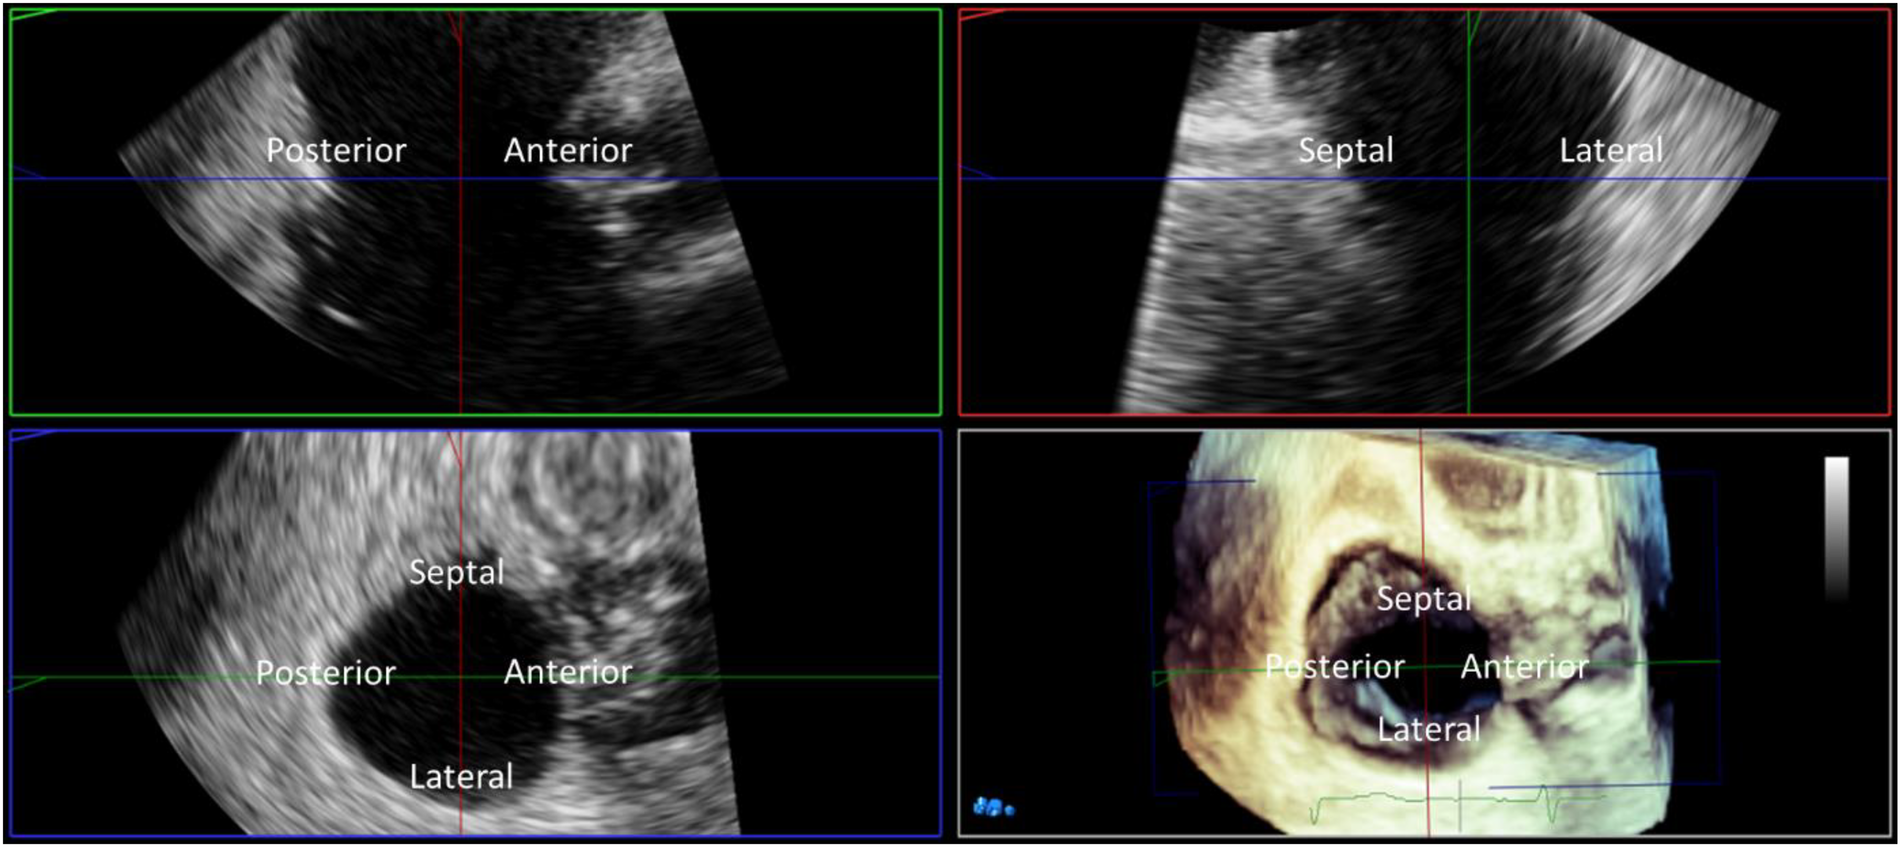

For quantitation assessment of the tricuspid valve, a 3D volume can be manipulated off-line using MPR. Measurement of annular area, perimeter and diameters, as well as quantitation of leaflet lengths and coaptation gaps are required for determining anatomic feasibility of device placement. For procedural guidance, real-time multiplanar imaging using MPR allows continuous imaging of four different views: two orthogonal 2-D long-axis views with the tricuspid annulus perpendicular to the ultrasound beam, a 2D short-axis view at any level of the tricuspid valve apparatus, and a 3D rendered image. The most useful 2D long-axis views are typically the inflow-outflow view imaging the anterior leaflet to the right, and posterior leaflet to the left of the sector, and the orthogonal 4-chamber view with “lateral” leaflet to the right, and septal to the left of the sector. The “lateral” leaflet can be either the anterior or the posterior leaflet depending on the where the orthogonal plane is placed on the inflow-outflow view. The short-axis view can be positioned at any level, from the narrow apex to the broad base of the volume, depending on the requirements of device positioning and anchoring; imaging the annular level is most useful for annuloplasty devices and orthotopic valve replacements whereas at the leaflet level may be optimal for TEER devices. The 3D rendered image can be defined by the user as any of the three 2-D images in the MPR screen but most often the short-axis 3D rendering is preferred for TEER devices to orient the device arms and for orthotopic valve replacements for positioning in the annulus. Importantly, all planes can be manipulated throughout the procedure to inform the proceduralist of device positioning relative to the tricuspid valve and surrounding anatomy.

Annular area by TEE can be estimated from 2D imaging by incorporating the anterior-posterior and septal-lateral annular diameters into the formula for an ellipse, or measured from 3D volumes (Figure 6). Two methods have been correlated with CT; direct annular area and perimeter planimetry of the tricuspid annulus from 3D multi-planar reconstruction of the short-axis annular imaging plane, or using in-direct measurement adapting the advanced mitral annular quantitation program (52). The in-direct measurement of the tricuspid annulus correlates best with CT measurements and may be used for device sizing, however direct planimetry of the annular area allows for a more accurate quantitation of diastolic stroke volume.

Figure 6

Three-dimensional (3D) TEE multiplanar reconstruction. 3D imaging with multiplanar reconstruction of the tricuspid valve from the mid esophageal window in mid diastole. The 3D block is presented in the ‘non rotated’ view with the reconstructed long axis 2D images displayed in the familiar ‘commissural’ and corresponding septo-lateral orthogonal image. Direct measurement of tricuspid annular dimensions is performed from planimetry of the 2D short axis image aligned with the tricuspid annulus.